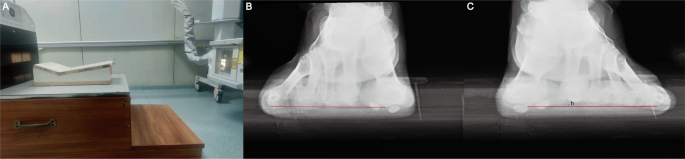

65 female and male patients (aged 27 to 73 years), or 77 feet, were evaluated. Standard weight-bearing anteroposterior radiographs were taken to evaluate the relative outcome measures for this study, such as the intermetatarsal angle (IMA) and hallux valgus angle (HVA). The relative height of the second metatarsal was also measured, and it was defined as the perpendicular distance of the second metatarsal head from the line that was connected to the lowest point of the first and fifth metatarsal heads (Fig. 4). The valid width of the first metatarsal was measured using the method shown in Fig. 5. The actual lateral transfer distance was recorded intraoperatively.

The height of the second metatarsal head. (A) A purposefully designed supporting plane was used to measure the height of the second metatarsal head. (B,C) The relative height of the second metatarsal head was defined as the perpendicular distance from the baseline, which was drawn between the lowest point of the fifth metatarsal head and first metatarsal head.